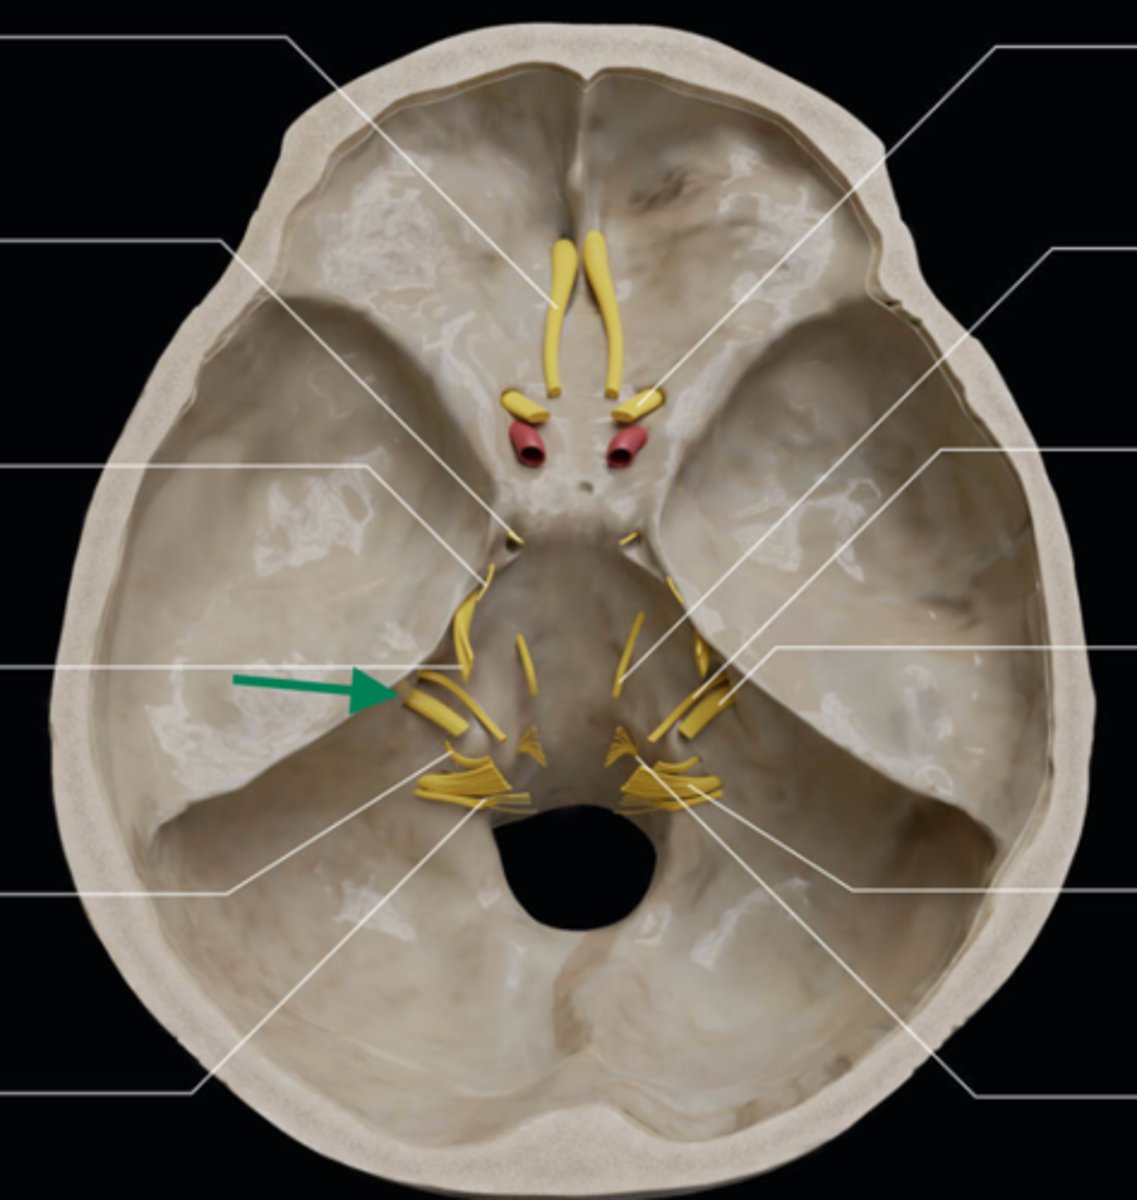

olfactory bulb

olfactory tract

optic nerve (CN II)

internal carotid artery

oculomotor nerve (CN III)

trochlear nerve (CN IV)

abducent nerve (CN VI)

trigeminal nerve (CN V)

facial nerve (CN VII)

vestibulocochlear nerve (CN VIII)

glossopharyngeal nerve (CN IX)

vagus nerve (CN X)

accessory nerve (CN XI)

hypoglossal nerve (CN XII)